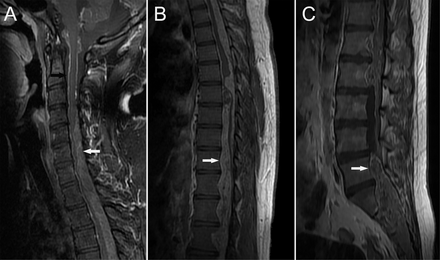

一名20岁男子看到一个月增加右腿无力和麻木的历史。有一个脊椎从C4远侧地提高质量(图1,a - c)和颅内传播(图2A和B)。病人接受了1-stage切除最大限度的保护功能,其次是放射治疗。病理证实诊断为myxopapillary室管膜瘤,1级(图2C)。少见的脊髓延伸到超过10椎段非常罕见,1,总计切除与全切除,放疗相比没有优势。2

图1

脊髓室管膜瘤图像

脊柱矢状t1加权磁共振成像(a - c)演示了一个类似硬膜内的质量不均匀增强信号,从C4水平延伸至远端脊柱(白色箭头)。未发现病变仅在C1级别C3水平(A,黑色箭头)。